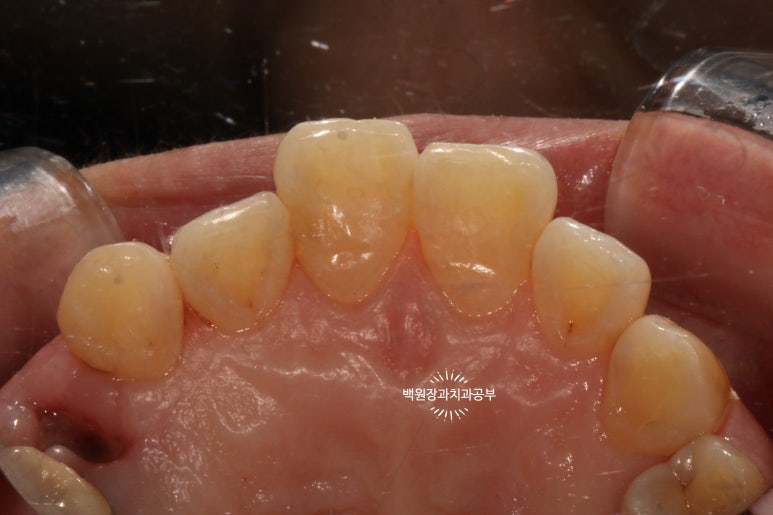

치료 전과 치료 후를 쉽게 비교하실 수 있도록, 치료 직전 찍어놓은 사진이에요.

상악 중절치와 측절치 그리고 견치에 옆면 모두에 충치가 있습니다.

위 앞니의 뒷면 사진이에요.

치아를 최소한으로 삭제하면서도, 어둡게 썩어있는 부위는 확실히 제거해야 최종 결과가 예쁘게 나온답니다.

아까 보았던 것처럼 뒷면에서 바라본 위턱 앞니입니다.

치과의사로써 앞니 레진치료를 할 때, 가장 어려운 부분이라면

충치가 있던 옆면을 정교하게 재현해내는 것이라고 할 수 있는데요,

일반적인 충치치료는 보이는 면을 채워넣는 것과 달리,

앞니 옆면 충치치료는 닿아있어 직접 만질 수 없는 면을 레진으로 채워넣어야 하기 때문에

정교하게 모양을 만들어내기가 무척 어렵습니다.